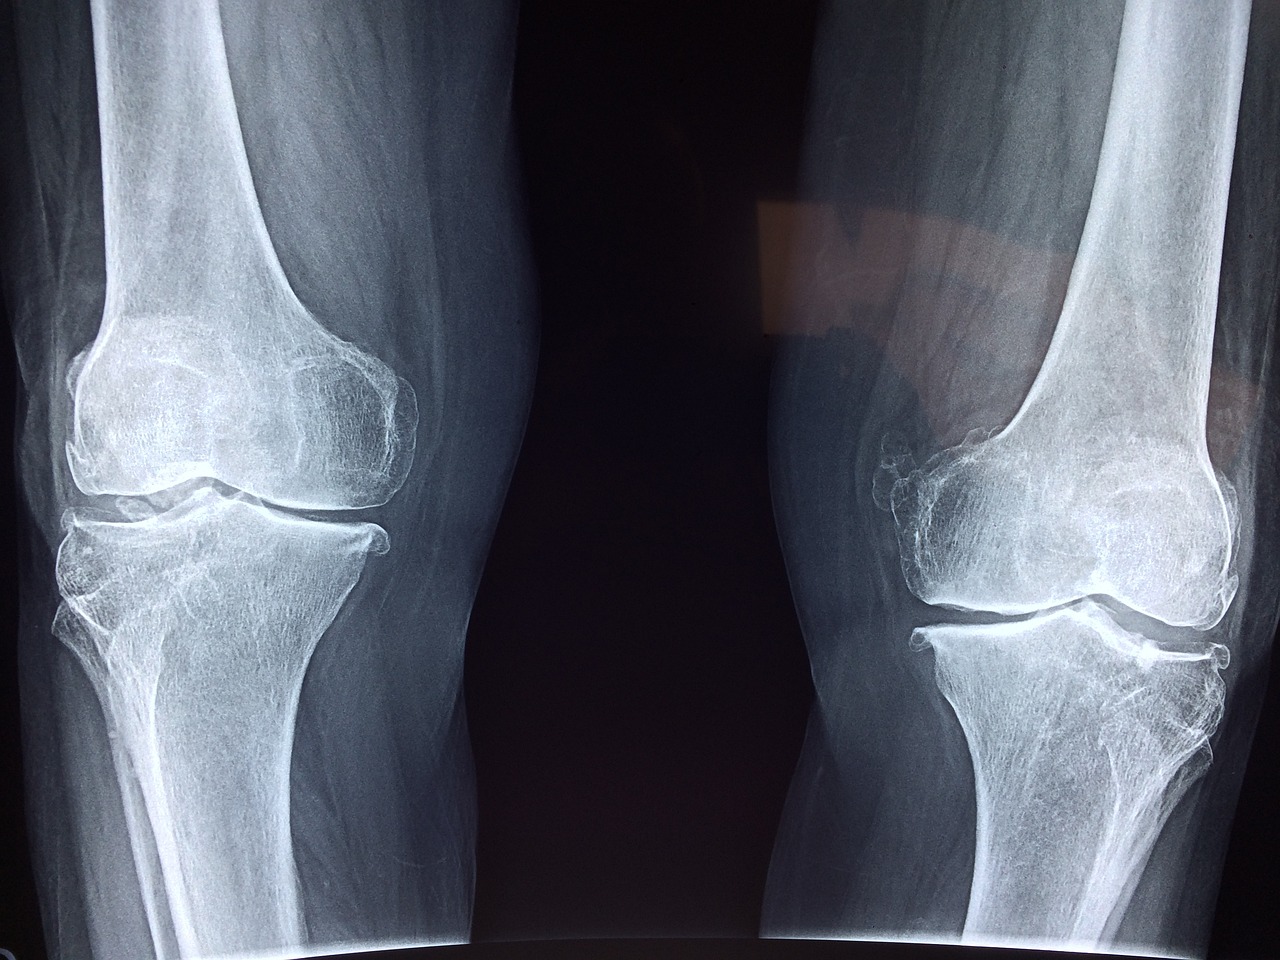

나이가 들수록 관절은 자연스럽게 퇴화하기 시작하며, 이는 일상생활의 불편함과 통증으로 이어질 수 있습니다. 따라서 관절 건강을 유지하는 것은 시니어 웰빙의 핵심 중 하나입니다.

두 번째로, 체중 관리가 중요합니다. 과체중이나 비만은 무릎과 엉덩이 관절에 과도한 압력을 가해 관절 손상을 가속화시킬 수 있습니다. 적정 체중을 유지하는 것은 관절의 부담을 줄이고, 관절염 같은 질환의 위험을 낮출 수 있습니다.